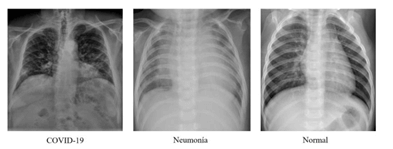

¿Cómo funciona este modelo? El modelo es con base a un sistema de inteligencia artificial que reúne muchas fotografías: 600 de personas con neumonía, 600 de personas con Covid-19 y 600 personas sanas. Haciendo la comparativa de las fotografías con los resultados de rayos x puede determinar si tu padecimiento es por coronavirus.

Hasta el momento tiene una precisión del 95%. No obstante, según informaron, cada vez las pruebas serán más precisas, ya que la base de datos se está alimentando constantemente con más fotografías lo que logra que los resultados puedan ser más confiables.